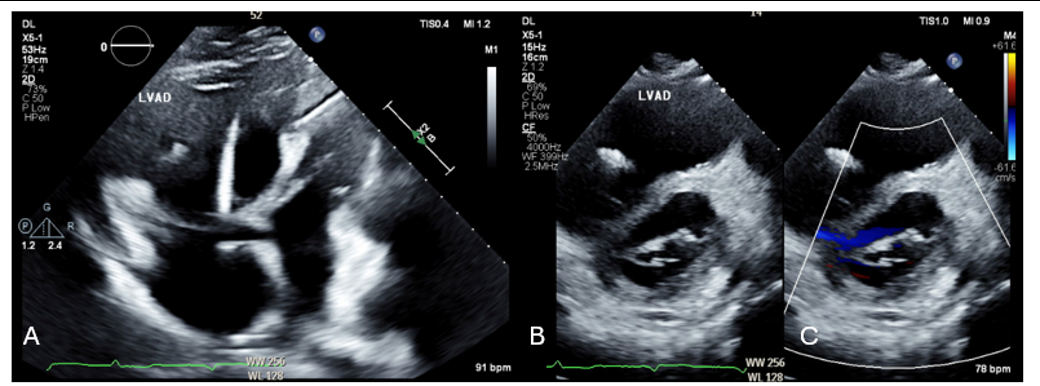

A 70-year-old male with HFrEF with CRT-D and HeartMate3 LVAD, RV failure status-post RVAD placement and recent explantation, presented after multiple ICD shocks. He initially presented in ventricular tachycardia (VT) at 200 bpm (Figure 1). Despite 3 attempts of DCCV and amiodarone infusion, he remained in VT. He was intubated to reduce sympathetic tone. A low flow alarm from the LVAD was noted. TTE showed a severely dilated RV with evidence of pressure overload (Figure 2). The patient also required rapid escalation of vasopressors. He was taken emergently for RHC and possible MCS placement.

The PA catheter was inserted and advanced to the wedge position in the PA via the right femoral vein. The calculated PAPi was 0.63, the CPO was 0.35, and the wedge pressure was 23 mmHg. A decision was made to place an Impella RP for biventricular shock in the context of a pre-existing LVAD.